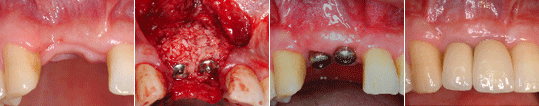

상실된 두 개의 앞니를 2개의 임플란트를 식립하여 회복한 증례

상한 앞니를 발거하고 즉시 임플란트를 식립하여 회복한 증례 - 상악동 거상술을 통한 골 이식술